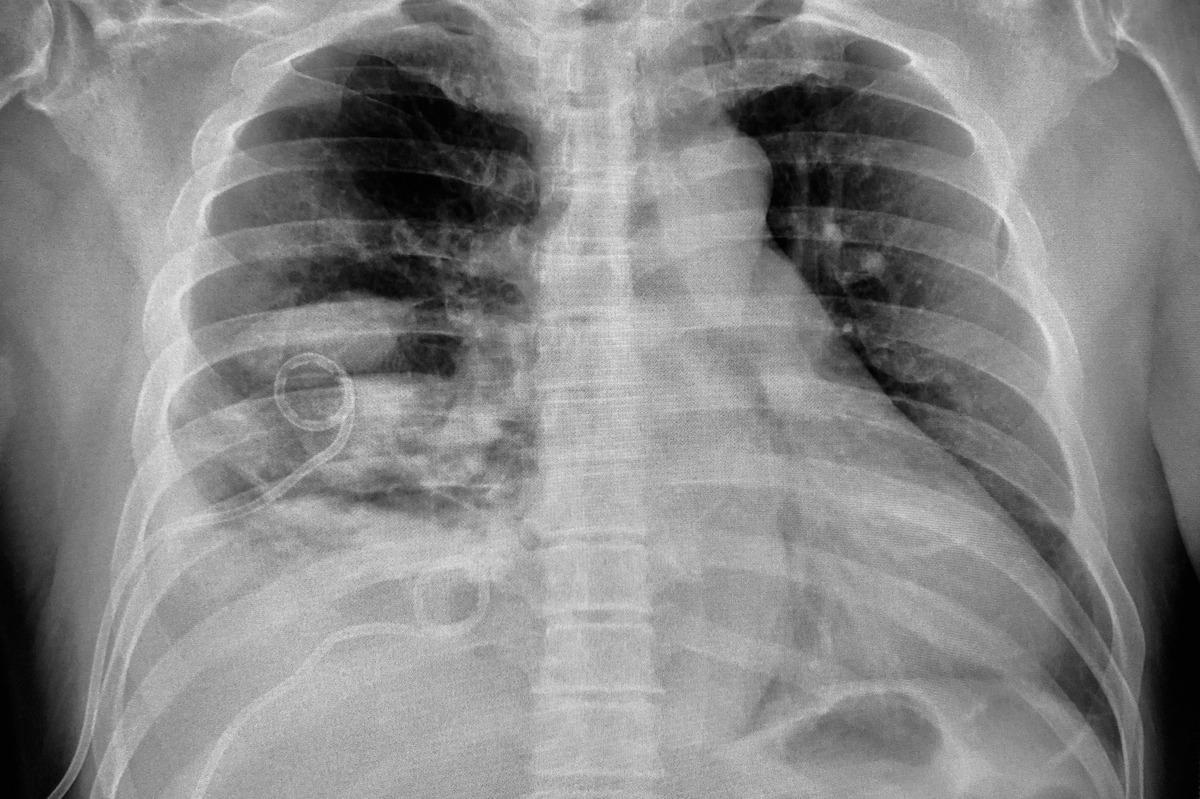

Empyema is a medical term used for pus pockets that have accumulated inside a body cavity, for example, pleural space. This condition occurs when a bacterial infection remains untreated or if it does not respond completely to treatment.

Empyema is a severe condition that necessitates medical attention. It can cause chest pains, coughing up mucus, fever, and shortness of breath.

Image Credit: ALIOUI MA/Shutterstock